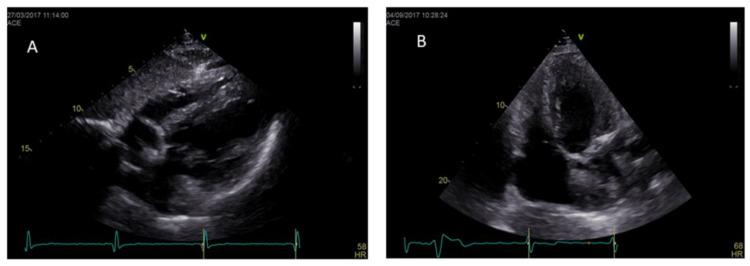

Anderson-Fabrydisease is an X-linked lysosomal storage disorder caused by a deficiency in the lysosomal enzyme α-galactosidase A. This results in pathological accumulation of glycosphingolipids in several tissues and multi-organ progressive dysfunction. The typical clinical phenotype of Anderson-Fabry cardiomyopathy is progressive hypertrophic cardiomyopathy associated with rhythm and conduction disturbances. Cardiac imaging plays a key role in the evaluation and management of Anderson-Fabry disease patients. The present review highlights the value and perspectives of standard and advanced cardiovascular imaging in Anderson-Fabry disease.

安德森-法布里病是一种X连锁溶酶体贮积症,由溶酶体酶α-半乳糖苷酶A缺乏引起。这导致糖鞘脂在多个组织中病理性蓄积以及多器官进行性功能障碍。安德森-法布里心肌病的典型临床表型是与节律和传导障碍相关的进行性肥厚型心肌病。心脏成像在安德森-法布里病患者的评估和管理中起着关键作用。本综述强调了标准和先进心血管成像在安德森-法布里病中的价值和前景。